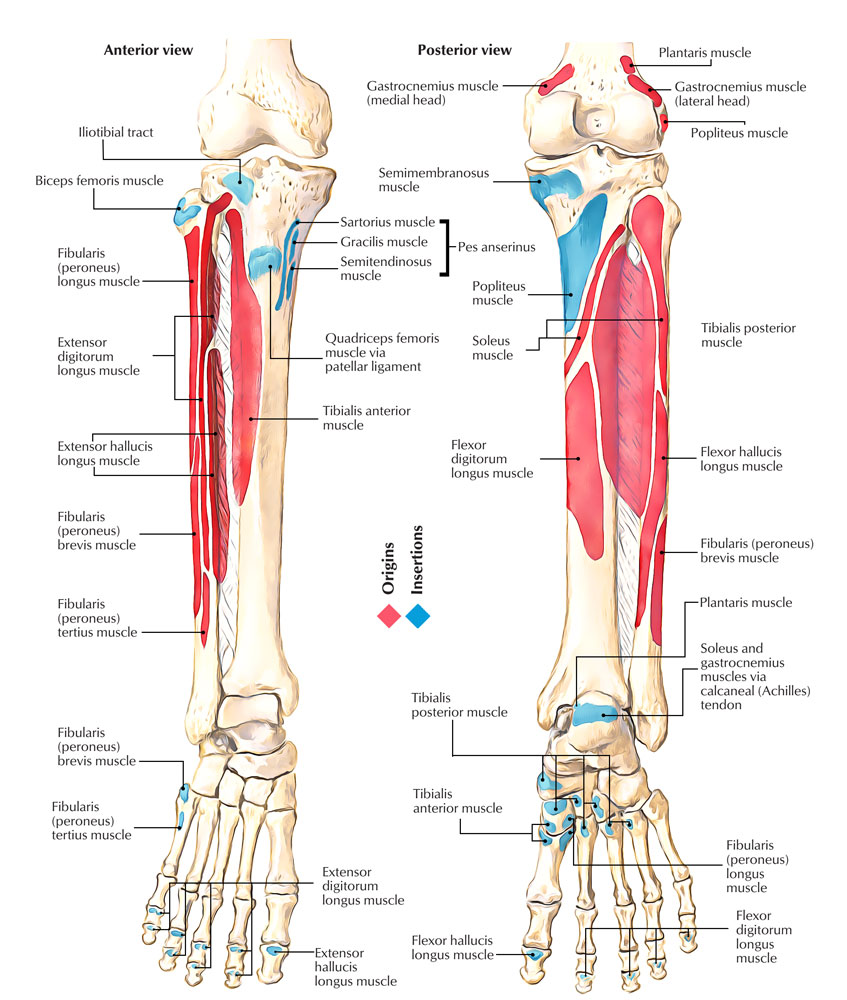

Anterior and posterior view of the tibia and fibula with labeling Stock …

Anatomy Tibia And Fibula Diagram | MedicineBTG.com

Tibia And Fibula Anatomy

Anatomy Stock Images | lowerleg-bones-tibia-fibula-front-skin-names

celebrity hollywood cool: Tibia And Fibula Posterior